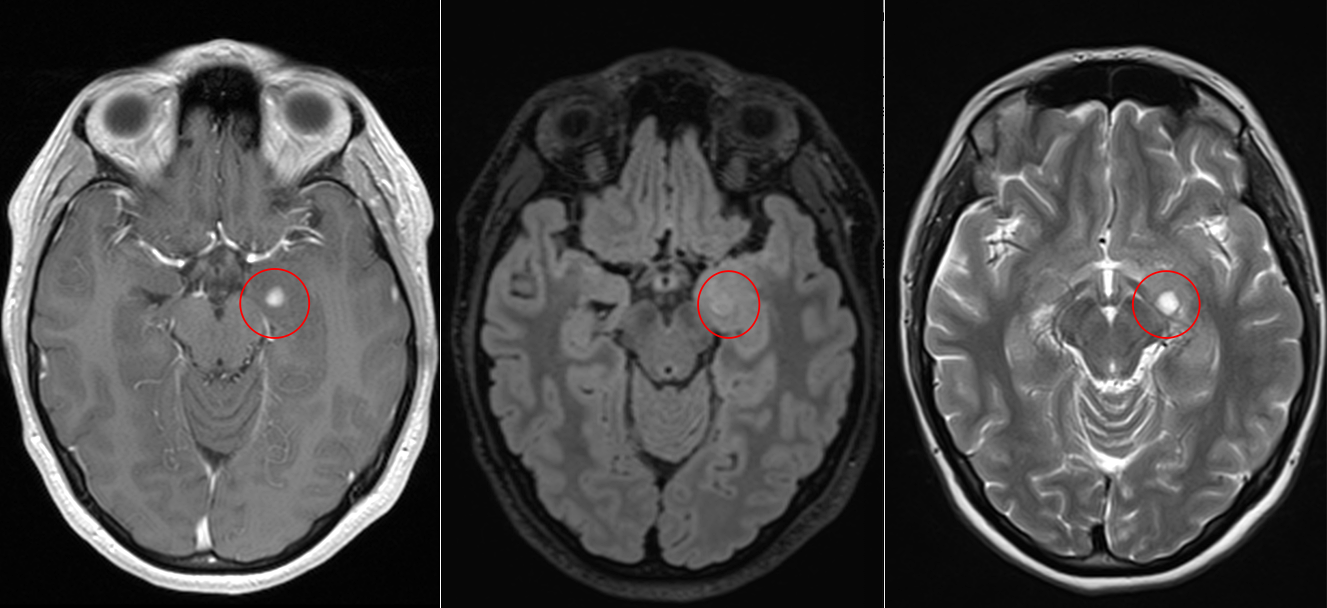

Pentru pacienți, aceste episoade sunt adesea greu de înțeles și pot fi însoțite de teamă și incertitudine. Investigațiile imagistice au adus însă explicația: RMN-ul cerebral a evidențiat o mică tumoră profundă, situată pe fața internă a lobului temporal stâng, la nivelul hipocampului și al nucleului amigdalian.

Deși tumora era relativ mică – aproximativ doi centimetri – localizarea ei era extrem de delicată. Hipocampul este una dintre structurile centrale ale creierului, implicată în memorie și procesarea emoțiilor, iar lobul temporal stâng joacă un rol important în limbaj.